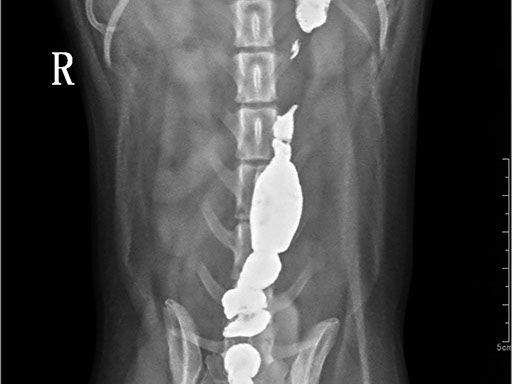

Коллиматорный прицел формирует пучок рентгеновского излучения на участок исследования. Проходя через ткани тела, излучение попадает на плоскопанельный цифровой детектор, который, в свою очередь, передает сигналы на компьютер.

В считанные секунды полученные данные обрабатываются компьютером посредством установленной на него программы визуализации, и сформированное клиническое изображение выводится на монитор лаборанта.

Клинические изображения (снимки) можно напечатать на принтере, сохранить в архиве или отправить по сети коллегам для оперативного консилиума.